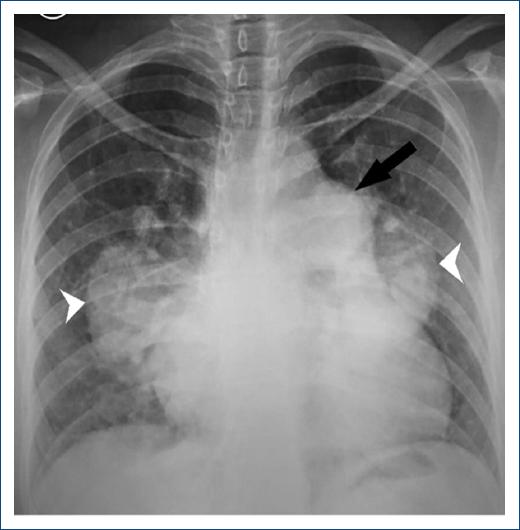

We present the case of a 35-year-old patient with neurological maturation retardation and a history of bicuspid aortic valve and subaortic membrane, who had started 15 days earlier with progressive dyspnea of functional class II to III-IV, orthopnea and angina in the last 24 hours. She had edema in the lower limbs, crackles in the lung bases, first and second tones present, and a tricuspid systolic murmur of 3/6 intensity with Rivero Carvallo's sign. The chest X-ray revealed cardiomegaly and dilatation of the pulmonary artery (Figure 1). Transthoracic echocardiography showed a preserved ejection fraction, systolic flattening of the interventricular septum, slightly dilated right ventricle with a 19 mm TAPSE, bicuspid aortic valve with preserved opening, with a small subaortic membrane, pulmonary, tricuspid, mitral and mild aortic aortic insufficiencies, PSAP 67mmHg, without intracardiac shunts. Acute pulmonary embolism was excluded by pulmonary angiography. The tomography showed a dilation of all the branches of the pulmonary artery (Figures 2 and 3). The right heart catheterization showed a mean pulmonary pressure (PAPm) of 52 mmHg, pulmonary capillary pressure (PCP) 13mmHg, pulmonary vascular resistance (PVR) 6 wood units, and cardiac index of 3.53 liters/minute/m2. Diuretic treatment with furosemide generated clinical improvement. Sildenafil and bosentan were subsequently started.

Figure 1 X-ray of the chest. Cardiothoracic index> 0.5, prominent main pulmonary artery (arrow) and dilated right and left pulmonary arteries (arrowhead).

This case is classified as a severe pulmonary hypertension precapillary phenotype of group 1.4.4 associated with congenital heart disease. The great dilation of the pulmonary artery and its branches led us to present chest radiography and pulmonary angiography images.